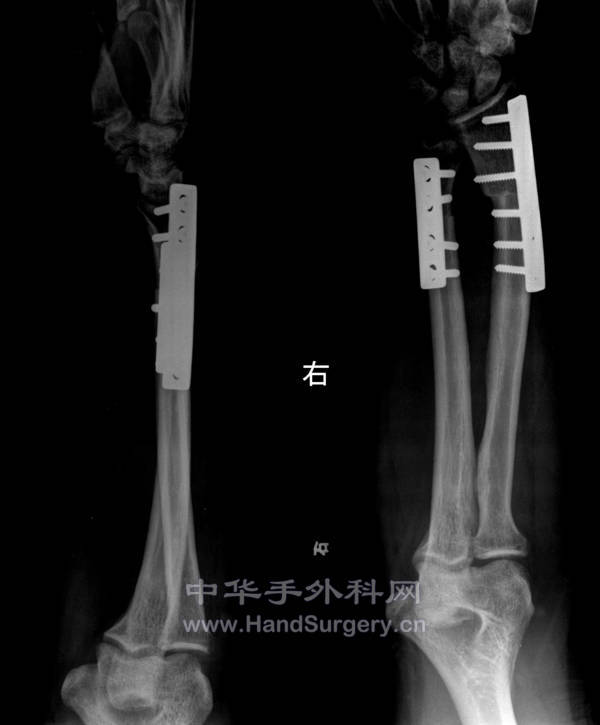

术后半年

术后半年.jpg

骨折是钢板固定的,局部皮瓣加植皮一期完成手术,其它待二期重建。